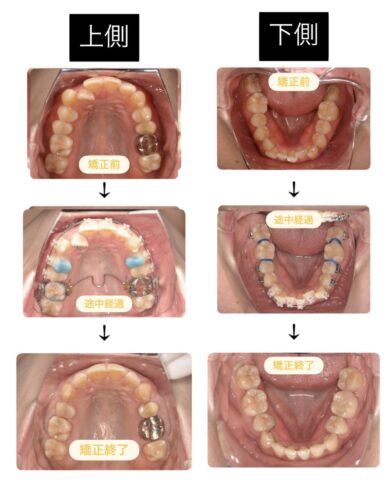

しっかりとアンテリアガイダンスを獲得できましたね!これで左側にかかっていた負荷を取り除けたので、残りの感染根管治療を行っていきます!

治療後は仮歯を入れて経過観察を行います!

その後、最終形のオールセラミックスを入れるための型どりをしました!

この方はこの2本の歯だけ神経を失ってしまいました。磨き方が悪くて虫歯になり神経を失ったのではありません。神経を失うほどの負担がかかっていたのです。矯正治療をせずに放置していたら神経を失うのはこの2本ではすまなかったでしょう、、